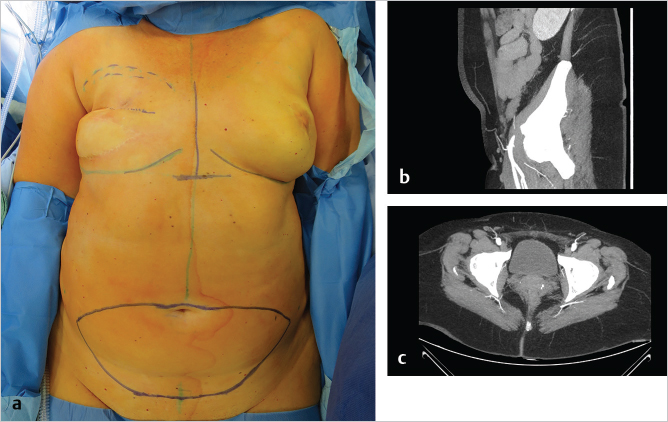

The patient is positioned supine on the operating table, and the lower abdominal skin island is outlined as for the DIEP flap (▶Fig. 56.2a). A preoperative CTA shows a sufficient SIEA and SIEV in the axial and sagittal view (▶Fig. 56.2b,c).